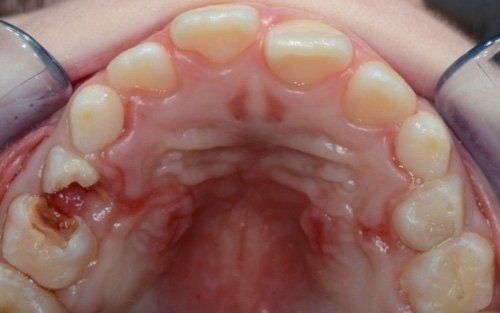

Spesso i dentini da latte cominciano a cariarsi già appena erompono nel cavo orale in quanto sono frequentemente a contatto con zuccheri semplici, come quelli veicolati dal biberon. Particolarmente aggressivi per i denti da latte risultano: tutte le tisane/infusi in commercio in bustine già pronte e pre-zuccherate; il latte zuccherato con qualsivoglia tipologia, incluso il miele; il latte e biscotti, specie nell’uso notturno; l’utilizzo quotidiano, spesso al posto dell’acqua, di succhi di frutta o bevande acide, per citare alcuni fra i più comuni errori commessi nel tentativo di dare una alimentazione completa al bambino, che spesso si traduce nella comparsa di una patologia chiamata